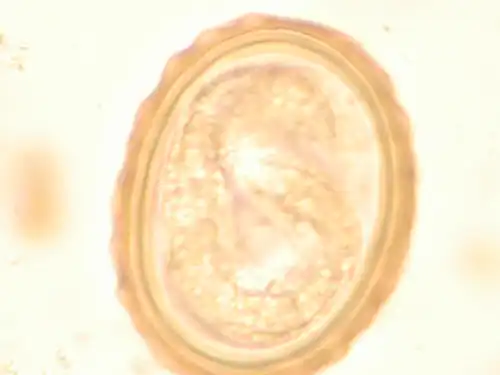

Most diagnoses are made by identifying the appearance of the worm or eggs in feces. Due to the large quantity of eggs laid, diagnosis can generally be made using only one or two fecal smears.[33] The diagnosis is usually incidental when the host passes a worm in the stool or vomit. The eggs can be seen in a smear of fresh feces examined on a glass slide under a microscope and there are various techniques to concentrate them first or increase their visibility, such as the ether sedimentation method or the Kato technique. The eggs have a characteristic shape: they are oval with a thick, mamillated shell (covered with rounded mounds or lumps), measuring 35–50 micrometer in diameter and 40–70 in length. During pulmonary disease, larvae may be found in fluids aspirated from the lungs. White blood cell counts may demonstrate peripheral eosinophilia; this is common in many parasitic infections and is not specific to ascariasis. On X-ray, 15–35 cm long filling defects, sometimes with a whirled appearance (bolus of worms).